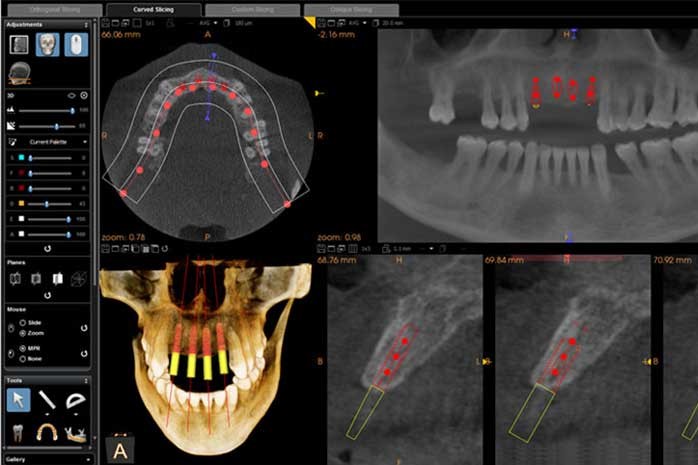

再來,透過電腦程式搭配 3D斷層掃描CT 的應用,可以準確地測量出齒槽骨立體的寬度與深度,以便找出最適當的植牙位置與角度。這些資訊也可判斷出植牙位置的骨頭條件是否足夠?如果需要補骨手術時,需要用何種的手術方式重建? 讓我們在手術之前就可以有一個精準的規劃。

依照電腦的規劃結果,可製做出需要的手術導引版和相關的植牙零件,使得手術結果與電腦模擬達到零誤差。